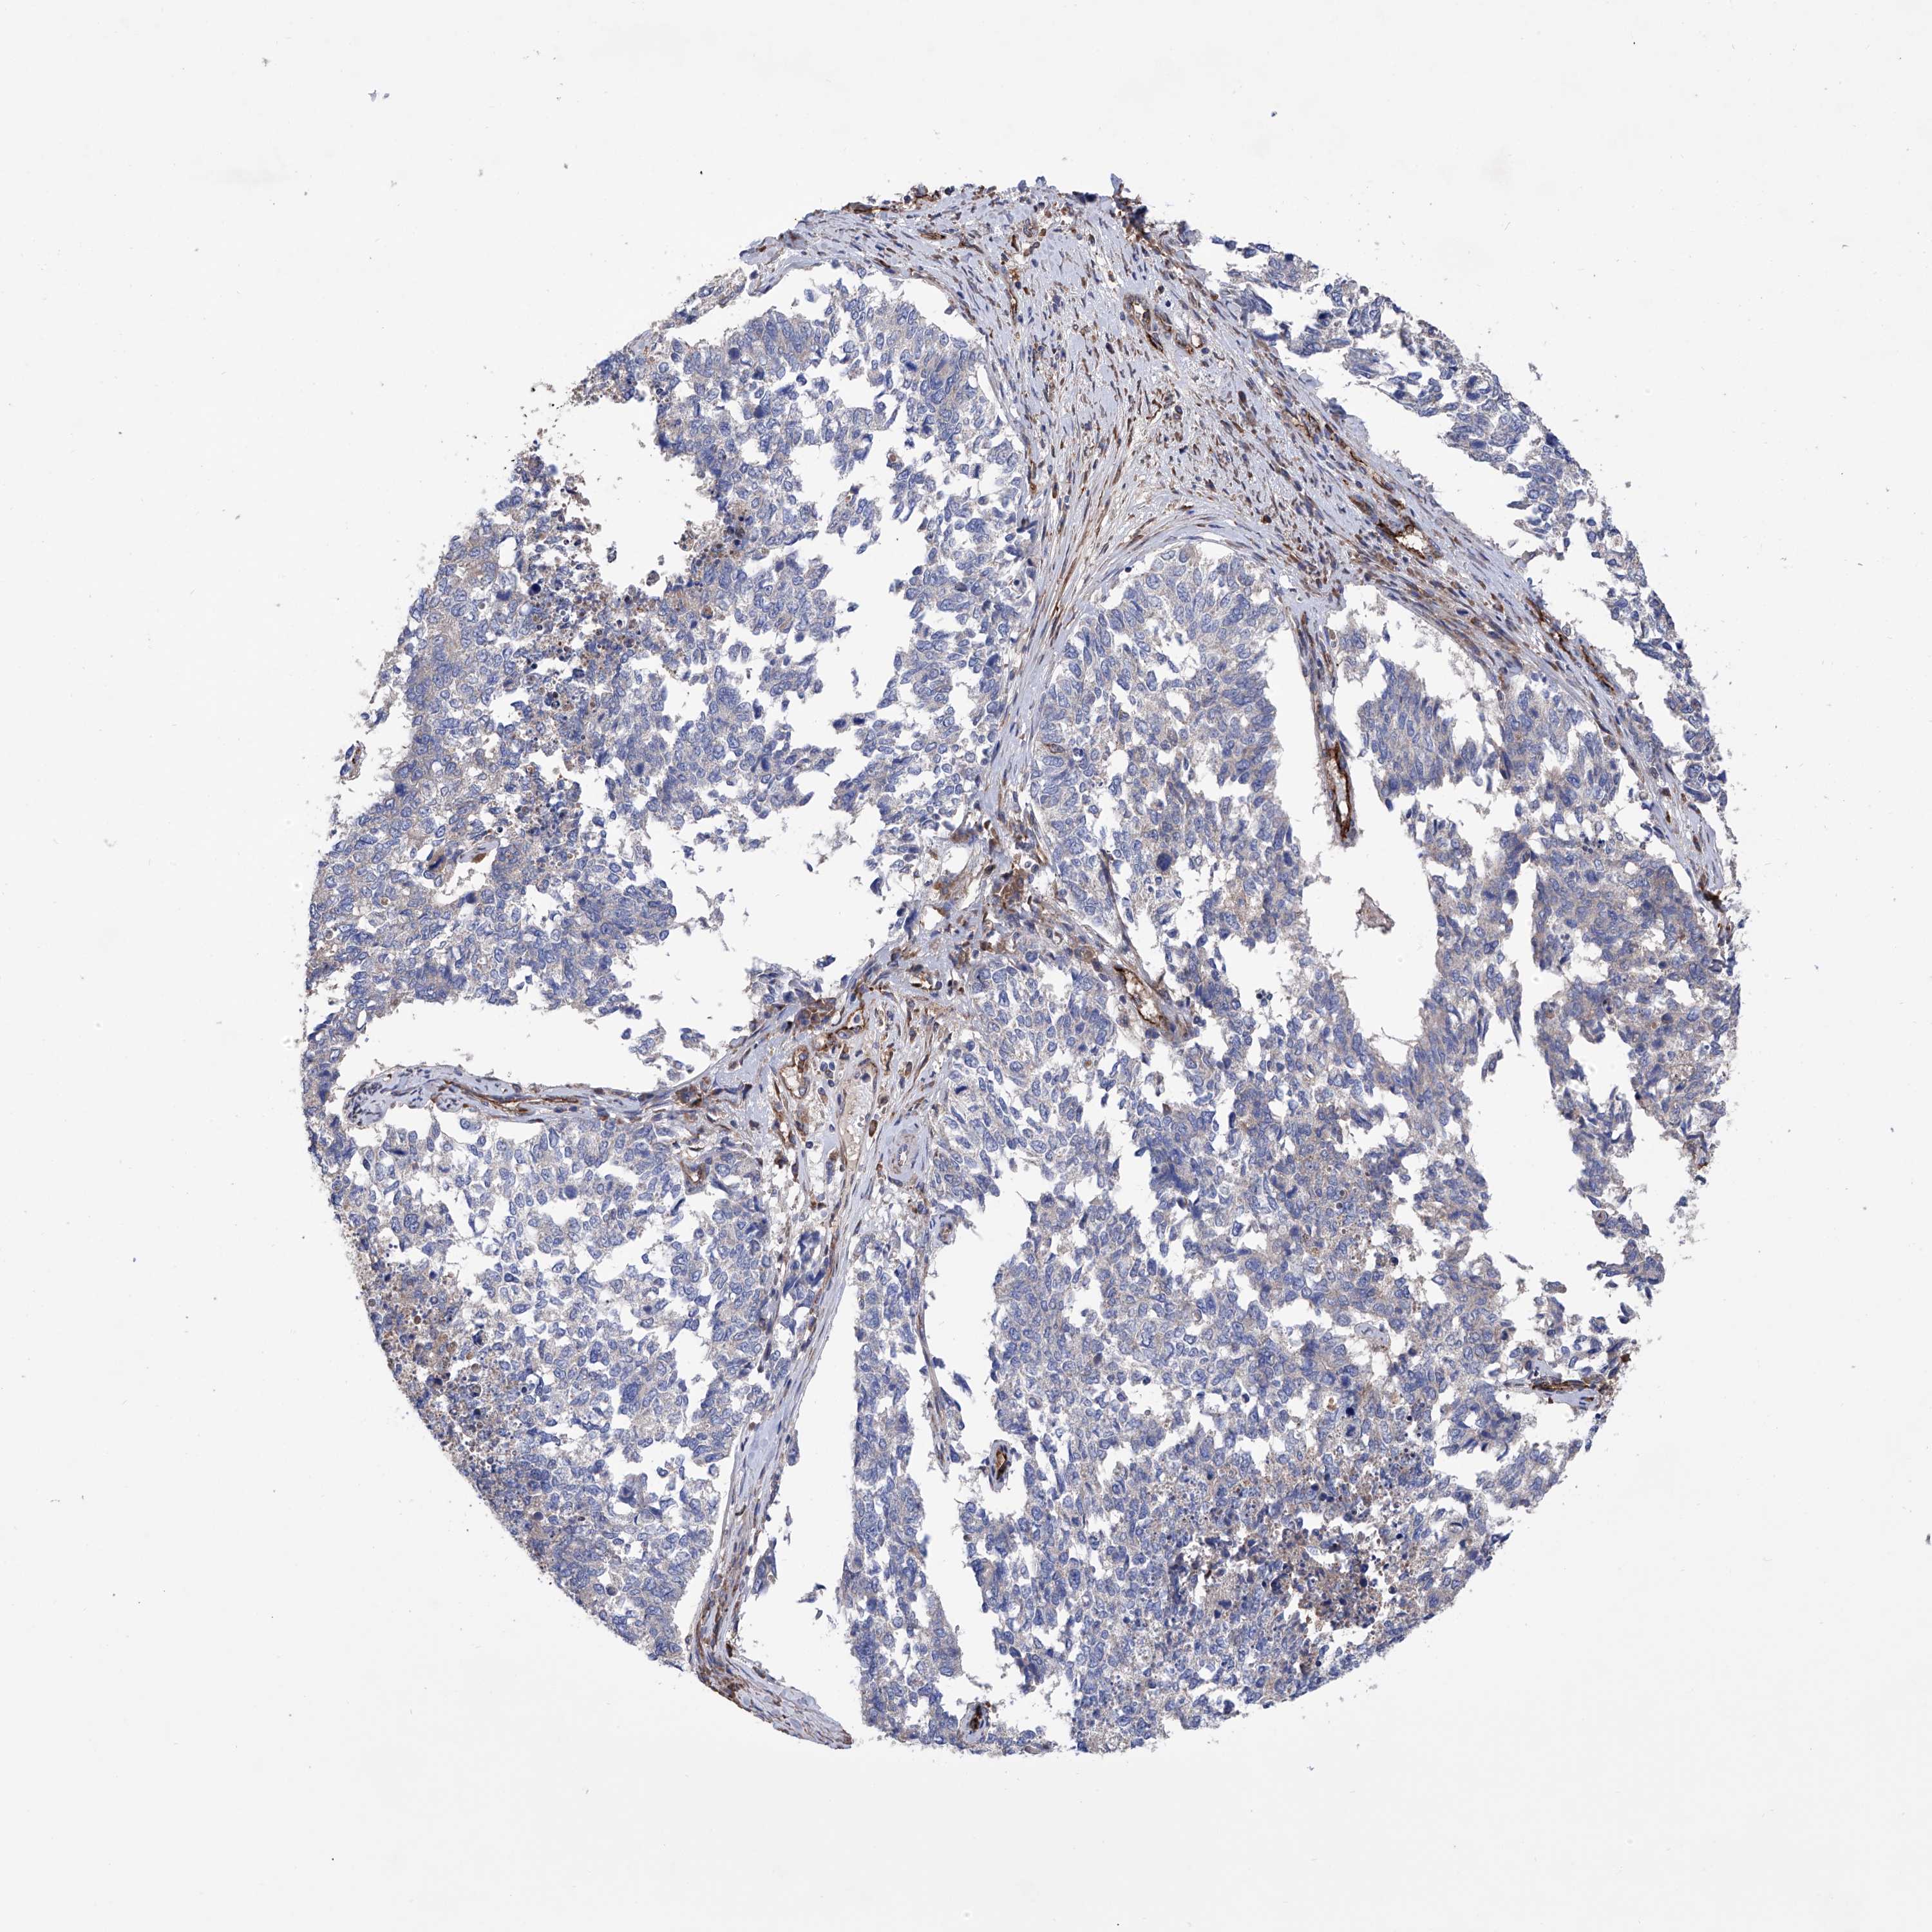

CERVICAL CANCER - Protein expressioni

A mouse-over function shows sample information and annotation data. Click on an image to view it in a full screen mode. Samples can be filtered based on level of antibody staining by selecting one or several of the following categories: high, medium, low and not detected. The assay and annotation is described here.

Note that samples used for immunohistochemistry by the Human Protein Atlas do not correspond to samples in the TCGA dataset.

Antibody stainingi

Antibody staining in the annotated cell types in the current human tissue is reported as not detected, low, medium, or high, based on conventional immunohistochemistry profiling in selected tissues. This score is based on the combination of the staining intensity and fraction of stained cells.

Each image is clickable and will lead to virtual microscopy that enables deeper exploration of all samples and also displays staining intensity scores, fraction scores and subcellular localization as well as patient and tissue information for each sample.

Antibody HPA028803

Staining

High

Medium

Low

Not detected

Intensity

Strong

Moderate

Weak

Negative

Quantity

>75%

75%-25%

<25%

None

Location

Nuclear

Cytoplasmic/membranous

Cytoplasmic/membranous,nuclear

Squamous cell carcinoma, NOS